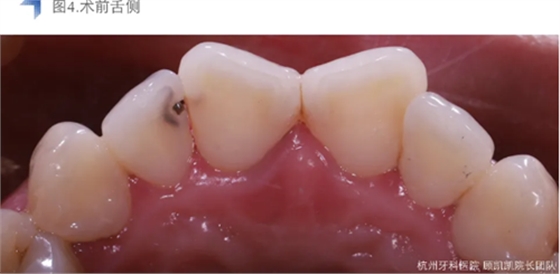

接诊后口内检查12近中邻面较大面积龋齿,探不适,叩无不适,冷热测试同时对照牙及临牙,BOP+,扪诊(-),未有异常松动度。术前CBCT检查如下图,未见明显根尖周透射影。

局麻橡皮障下去龋尽,极尽髓,iroot bp+盖髓,上面覆盖bisco硅酸钙,流体树脂洞型重建后贴面预备,排龈后Cerec Omincam光学取模,3D打印树脂模型以检查修整瓷贴面。